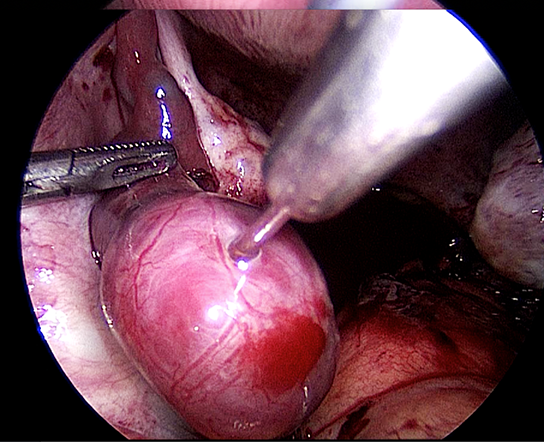

Kehamilan spontan setelah Salpingostomi Laparoskopi untuk tuba kehamilan ektopik

NMA, merupakan seorang wanita yang berusia 33 tahun dan berkonsultasi kepada saya untuk pertama kalinya di tahu 2013. Dia sedang hamil 8 minggu. USG telah menunjukkan 2 kantong kehamilan yang terbentuk dengan baik tetapi tidak ada aktivitas pada janin. Dia menjalani kuretase hisap. Pasca operasi kondisi dia dalam keadaan yang baik dengan periode menstruasi yang teratur. Enam bulan kemudian dia mengalami nyeri panggul. Dia telah melewatkan menstruasinya dan test kehamilan menunjukkan hasil yang positif. USG menyatakan ukuran rahim normal tanpa kantong kehamilan intrauterin dan massa pada adneksa kiri dengan cairan di kantong Douglas. Diagnosis kehamilan ektopik telah dibuat.Dia menjalani salpingostomi laparoskopi ( simak video 26.2 ) . Pasca operasi kondisi dia baik-baik saja. Enam bulan kemudian dia menjalani histerosalpingogram ( HSG ) dan HSG menunjukkan tuba kanan paten , tuba kiri dapat dilihat tetapi tidak ada tumpahan perwarna. Dia menjalani inseminasi intrauterin sebanyak satu siklus namun itu dilakukan tanpa adanya keberhasilan. Dia hamil secara spontan dan empat bulan kemudian dan telah melahirkan bayi perempuan sehat pada tahun 2015.

2 tipe operasi / pembedahan yang dapat dilakukan untuk kehamilan ektopik adalah (1) salpingostomi laparoskopi dan (2) salpingektomi laparoskopi. Salpingostomi laparoskopi hanya dapat dilakukan apabila tuba falopi tidak ruptur / pecah . Keunggulannya adalah pasien akan tetap memiliki tuba. Meskipun sakit, Dia mungkin bisa hamil secara spontan dengan tuba yang dioperasikan. Metode ini biasanya dipertimbangkan saat pasien hanya memiliki 1 tuba normal dan kehamilan ektopik terjadi di tuba itu. NMA ingin mempertahankan tubanya sehingga salpingostomi dilakukan. Dia akan menangung resiko kehamilan ektopik kedua yang berkembang di dalam tuba yang dioperasikan,namun beruntungnya dia hamil dengan kehamilan intrauterin dan telah melahirkan seorang anak.